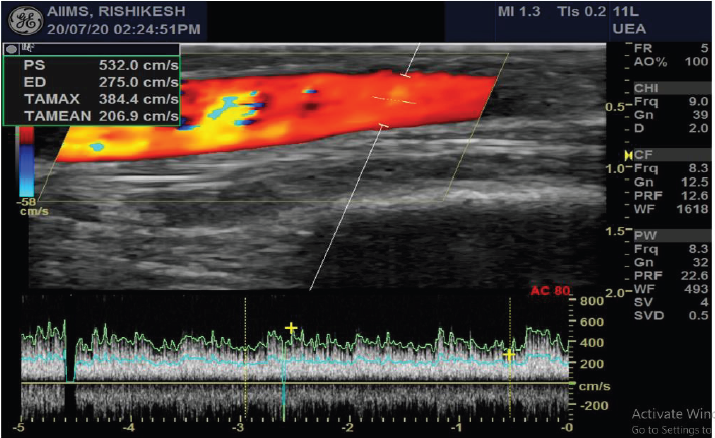

If right IJV is thrombosed, then IR accesses right External Jugular vein (EJV). If right side neck veins are thrombosed, then IR accesses left side neck veins: IJV or EJV (Figure 2). These tunnelled CVC are usually of size 14.5 French, with length 19, 23 or 27 cm, depending on patient’s height and from which side, neck vein is to be accessed. The cuff of tunnelled CVC is believed to prevent transmission of infection and also helps in securing CVC. If properly taken care of, then these tunnelled CVC can be used for 6-12 months. IR helps in managing these tunelled CVC, if flow rate is slow, by repositioning these CVC (Figure 3). IR have important role to play in managing AVF with slow flow rates. Most of times, stenosis is seen in these AVF, near anastomotic site. These juxta anastomotic AVF can be managed by IR by Percutaneous Transluminal Angioplasty (PTA), using appropriate size balloon. Some AVF show aneurysmal formation on venous side and these aneurysms can be managed successfully by IR (Figure 4). Sometimes, steal syndrome can be seen in AVF, due to reversal of flow in artery distal to anastomotic site. In case of steal syndrome, IR can block venous side using coils, in case of side to end AVF. This will increase flow rate in distal artery and reduce flow in fistula. In case of side-to-side AVF with steal syndrome, IR can successfully divert blood flow towards distal artery, by blocking collateral draining vein, distal to side-to-side anastomosis (Figure 5). If there is evidence of central vein stenosis, then IR can do PTA of central vein (Figure 6). If there is evidence of elastic recoil, with residual stenosis more than 30%, then IR can manage central vein stenosis by using metallic stent (Figure 7). Herein, it is important to stress upon Doppler and Spectral waveform, which helps IR to manage these dialysis fistula and graft [3-5]. In mature fistula and graft, inflow artery shows monophasic flow, with raised Peak systolic velocity (PSV) and End Diastolic velocity (EDV), with spectral broadening (Figure 8). In artery distal to anastomotic site, biphasic or triphasic waveform may be seen. On venous side, spectral waveform shows monophasic flow with turbulent arterial waveform (Figure 9).

Figure 8: Radio-cephalic fistula with monophasic flow in inflow artery, with raised PSV & EDV and spectral broadening.